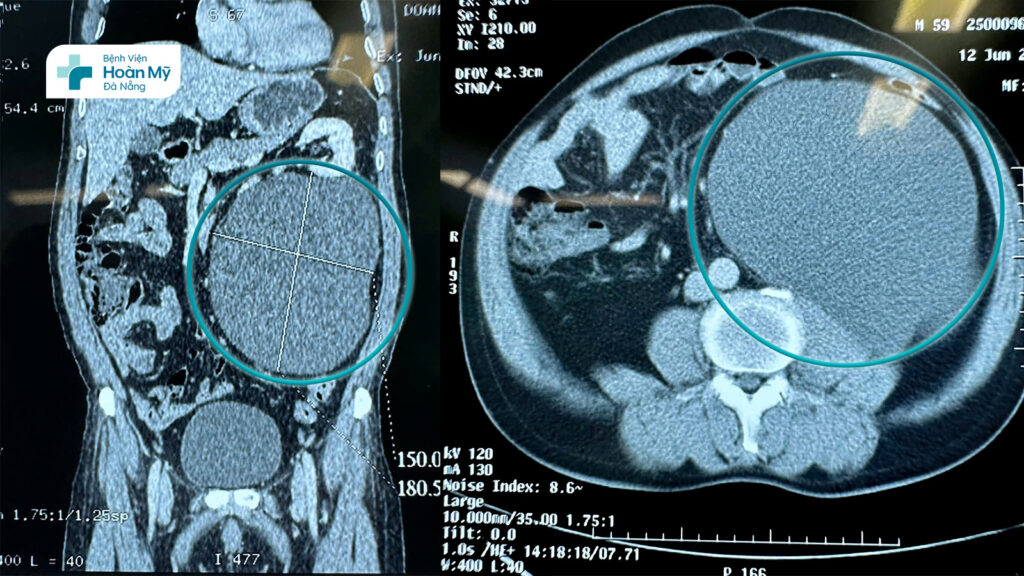

BS.CKI. Bùi Quốc Triệu – Trưởng khoa Ngoại Tiết niệu – Nam khoa, Bệnh viện Hoàn Mỹ Đà Nẵng chia sẻ: "Đây là khối u nang sau phúc mạc trái, kích thước lớn 150 x 180 mm và khá hiếm gặp. Khối u choán gần như hết nửa trái khoang bụng, chứa dịch đã chèn ép tạng ổ bụng, đẩy thận trái lên cao. Trong quá trình bóc tách nhận thấy đây là một khối u nang chứa dịch trắng đục hướng đến u nang bạch huyết dưỡng chấp, bác sĩ phải rất cẩn thận để loại bỏ hoàn toàn khối u để tránh tái phát và ngăn ngừa biến chứng xì dò hạch bạch huyết sau phẫu thuật. Nếu phẫu thuật cắt hoàn toàn nang mà không tổn thương các cơ quan lân cận, nguy cơ tái phát rất thấp."

Ekip mất hơn 1 giờ 30 phút tiến hành phẫu thuật nội soi sau phúc mạc bóc khối u nang với 3 lỗ trocar. Quá trình bóc tách khá thuận lợi như dự kiến, nhưng do kích thước quá lớn nên các bác sĩ đã tiến hành chọc hút chủ động sau đó bóc trọn vẹn màng u mà không ảnh hưởng đến các cơ quan lân cận. Về đại thể hút ra 2,7 lít dịch dạng sữa đục, xét nghiệm dịch vô trùng, chứa nhiều tế bào lympho, màng u cũng được gửi làm giải phẫu bệnh lý và cho về kết quả lành tính.

(hình 2) Hình ảnh khối u nang sau phúc mạc trong phẫu thuật